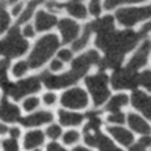

Step2. 對圖像進行二值化處理,區(qū)分出骨組織和髓腔

切片圖二值化處理